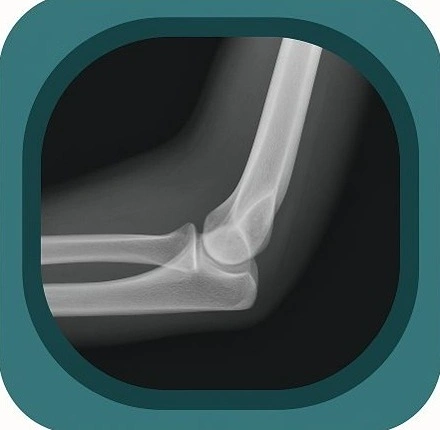

Explore high-quality X-ray anatomy from head to toe. Our database features carefully labelled images to visualize fine structuresโ€”perfect for radiologists, students, and surgeons.